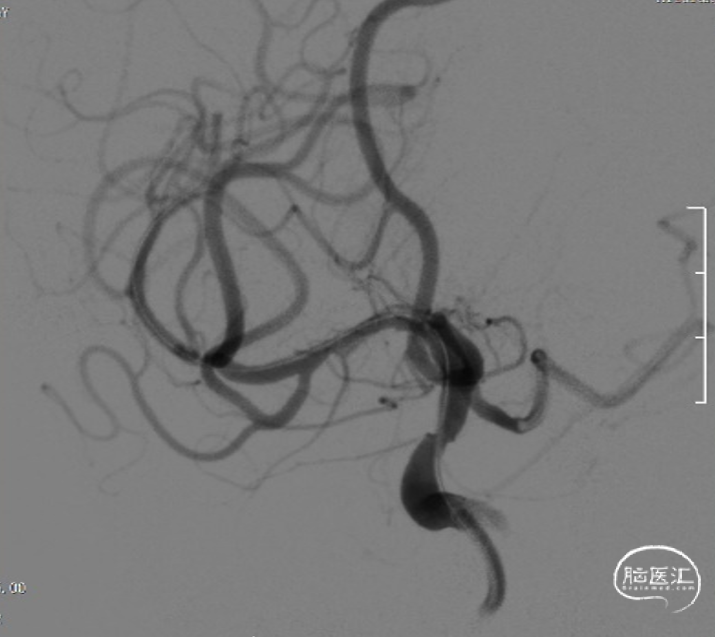

支架植入后造影及3D。

支架植入

支架植入后

术后即刻复查头颅CT未见异常。

术后定期门诊随访,1月以来患者未诉不适,头晕好转,肢体麻木感消失。